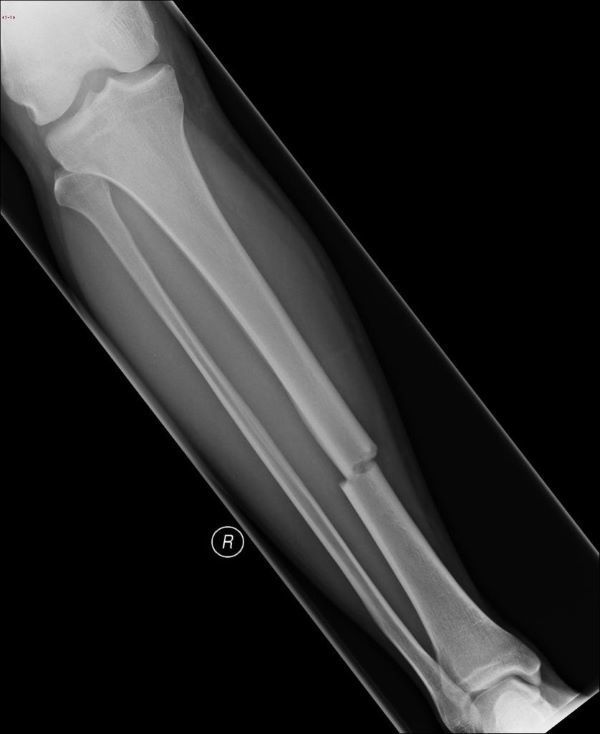

Fractura Transversal Mecanismo: Tension La linea de la fractura es mas o menos perpendicular al eje del hueso Fractura Espiral Mecanismo: Rotacion Se produce al rededor del hueso, afecta nervios y vasos sanguineos

Fractura Conminuta Mecanismo: Angulacion y Compresion Se astilla y rompe en mas de 2 piezas Fractura Oblicua Mecanismo:Compresion Se rompen de manera inclinada, crea saliente triangular

Fractura: Oblicua a 45º Mecanismo: Rotación más angulacióm Fractura: De dos componentes. Transversal/Oblicua 45º o ala de mariposa Mecanismo: Angulación más compresión